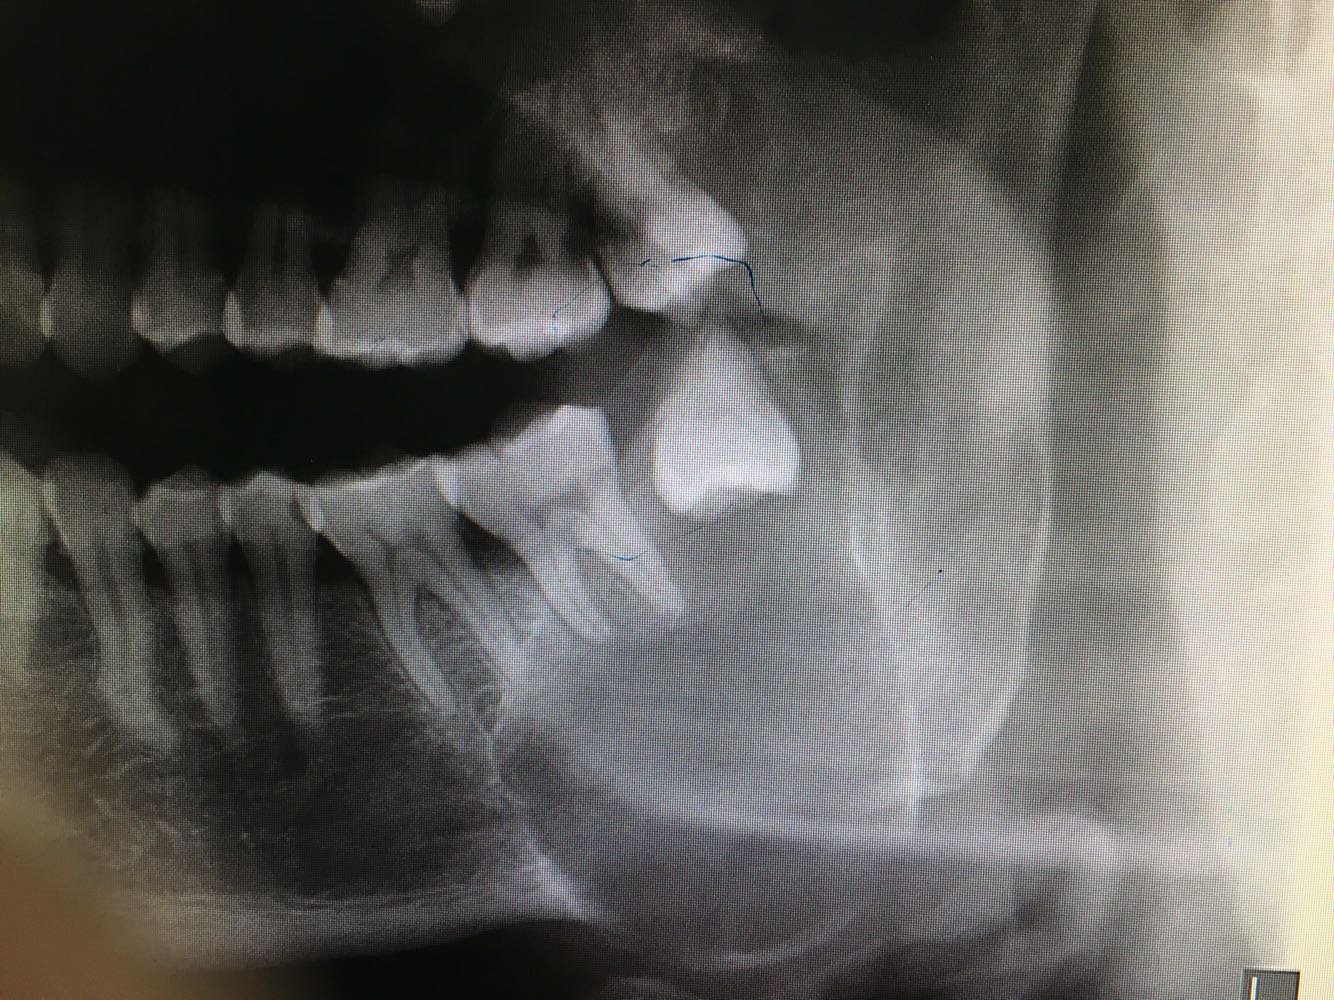

含牙囊肿_角化囊肿

简介:含牙囊肿(dentigerous cyst):世界卫生组织又将其称为滤泡囊肿(follicular cyst)。发生于牙冠牙釉质形成之后

简介:含牙囊肿是指环绕着未萌出牙或额外牙的牙冠,且附着于牙颈部的囊肿,属于牙源性囊肿。一般多发生于下颌骨,占含

答:隆起表面光滑、乒乓球感或破鸡蛋壳感。可出现病侧鼻塞和眼球向上移位。 含牙囊肿发病年龄高峰在10~39岁;在儿童期,含牙囊肿的发生率较其他颌骨囊肿略高。男性患者多